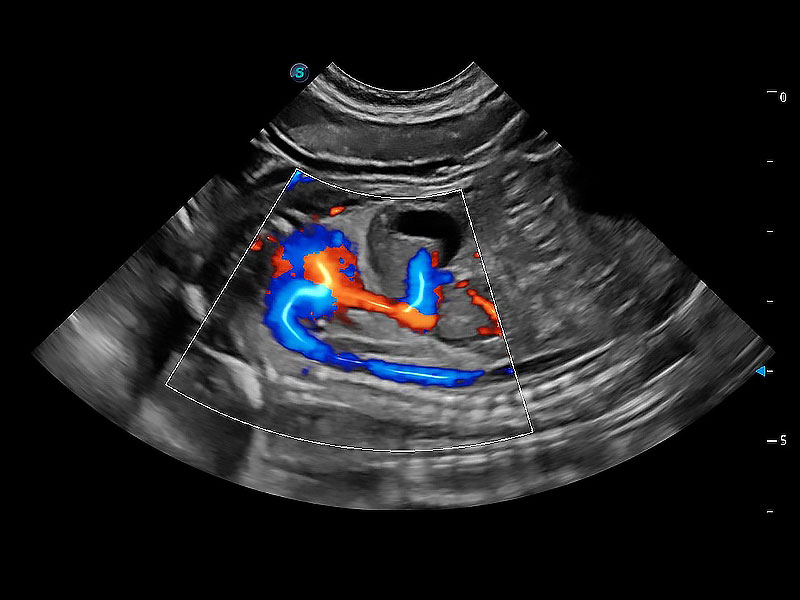

优异的基础图像

ProPet 80 全新的动物超声智能软件和丰富的探头群,为动物医生提供了高清晰度和精细分辨率的图像,无论在宠物、马科、畜牧还是实验室动物等应用中都可以轻松应对,为您的日常工作带来满意的体验。

(犬)胎儿四腔心